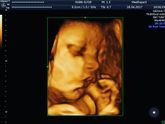

6 апреля 2017 12:48 Девочки 29 недель сильно тянет низ живота поясницу тоже ,с первой беременностью такого не было (